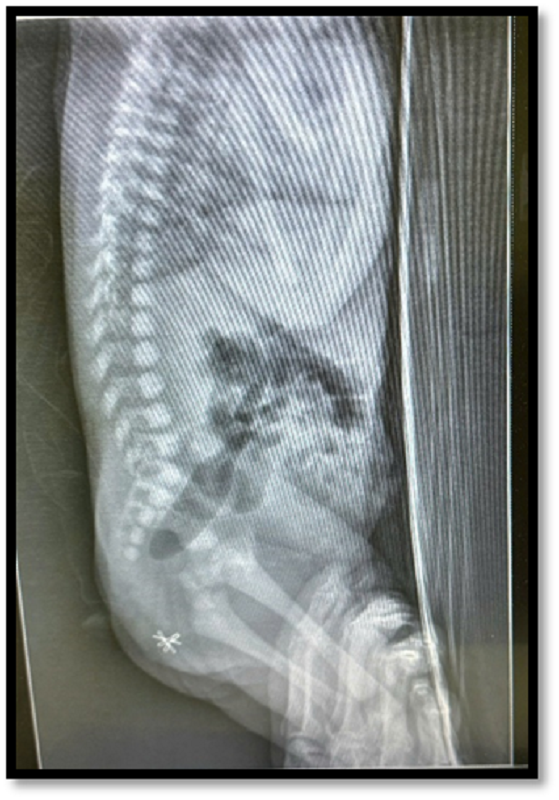

Hình ảnh kiểm tra ghi nhận, trẻ chào đời trong tình trạng không có hậu môn